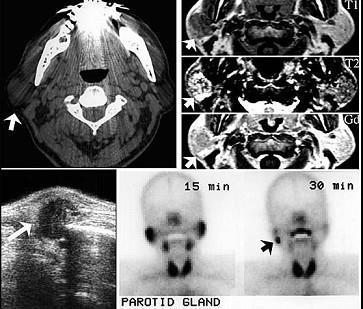

问题 60岁男性,左耳垂下无痛性肿物缓慢长大四年,局部有胀感。检查见肿块位于腮腺后下极,表面光滑,质中偏软,不可压缩,与皮肤无黏连。影像检查结果如图。最可能的诊断是 ( )

选项 A.腮腺血管瘤 B.腮腺多形性腺瘤 C.腮腺沃辛瘤 D.腮腺内淋巴结炎 E.腮腺囊肿

答案 C